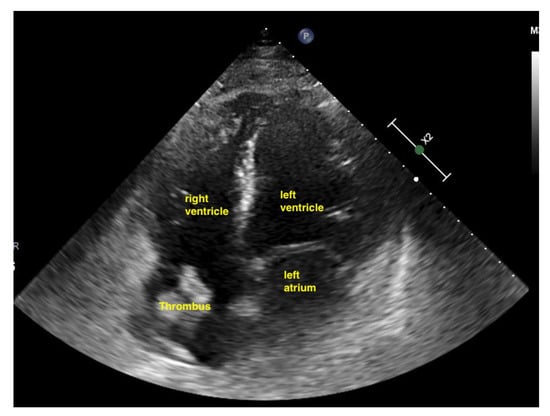

Figure 17.

Thrombus in the right atrium in acute pulmonary embolism.